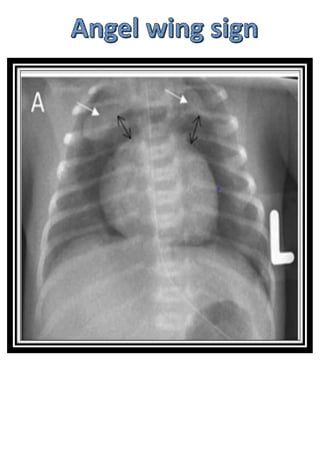

Stage iii Advanced NEC

iiia: peritonitis , ascites

PNEUMOPERITONEUM

STAGE IIIB NEC

AIR UNDER DIAPHRAGM

Radiographic features

Although these are essentially the

same as in adults, erect chest X-rays

are not obtained, and thus the

diagnosis should be made with supine

films. Additional horizontal cross

table shoot through films or left

decubitus shoot though films may be

performed.

Signs

•football sign

•Rigler's sign